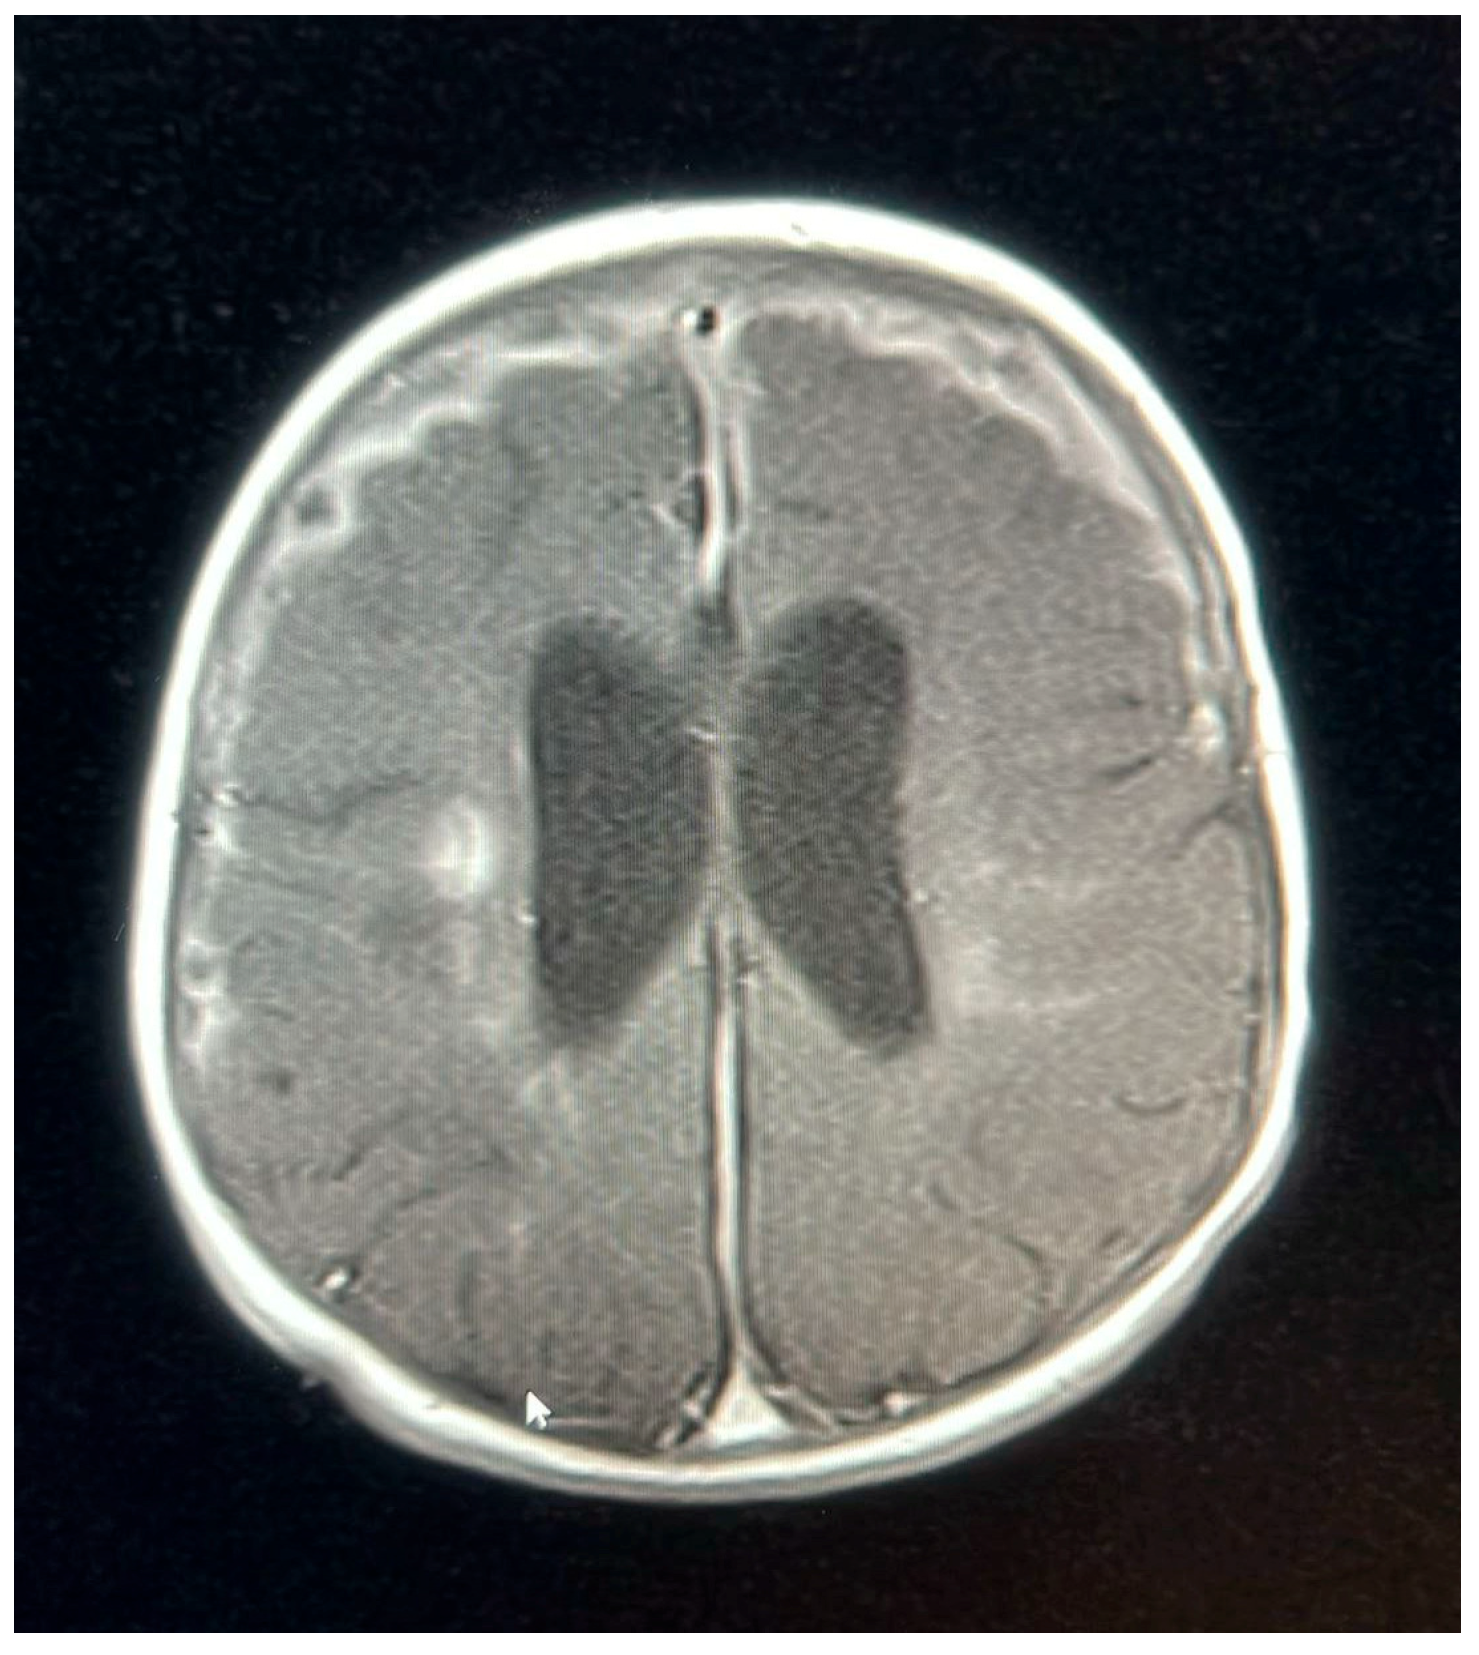

A follow-up MRI on 9 October 2022, 2 weeks later, showed new subdural empyemas and worsening meningitis. The small abscess-like lesions near the ventricles had grown slightly compared to the earlier scan. Signs of previous hypoxic–ischemic injury were observed, with some improvement, including reduced swelling and improved blood flow in the periventricular white matter and posterior parietal lobes. The basal ganglia lesions could represent small abscesses, brain infection (cerebritis), or subacute strokes. The neurosurgical team determined that the patient did not require surgical intervention, as the empyema was not causing a mass effect and the patient remained clinically stable. The patient was continued on meropenem for 6 weeks, as a second MRI and after 2 weeks of proper treatment showed new collections, while ganciclovir was discontinued after the patient received 21 days of treatment.

An MRI repeated on 11 November 2022, after 7 weeks of treatment, showed interval resolution of the abscesses and subdural empyema, with resolution of leptomeningeal disease. Expected changes were observed, including brain volume loss and periventricular leukomalacia, with the previously described foci of enhancement. The internal auditory canals appeared unremarkable (Figure 1, Figure 2, Figure 3, Figure 4 and Figure 5).

Figure 2. MRI brain scan showing meningeal enhancement.

Figure 3. MRI brain scan showing worsening of leptomeningeal enhancement.